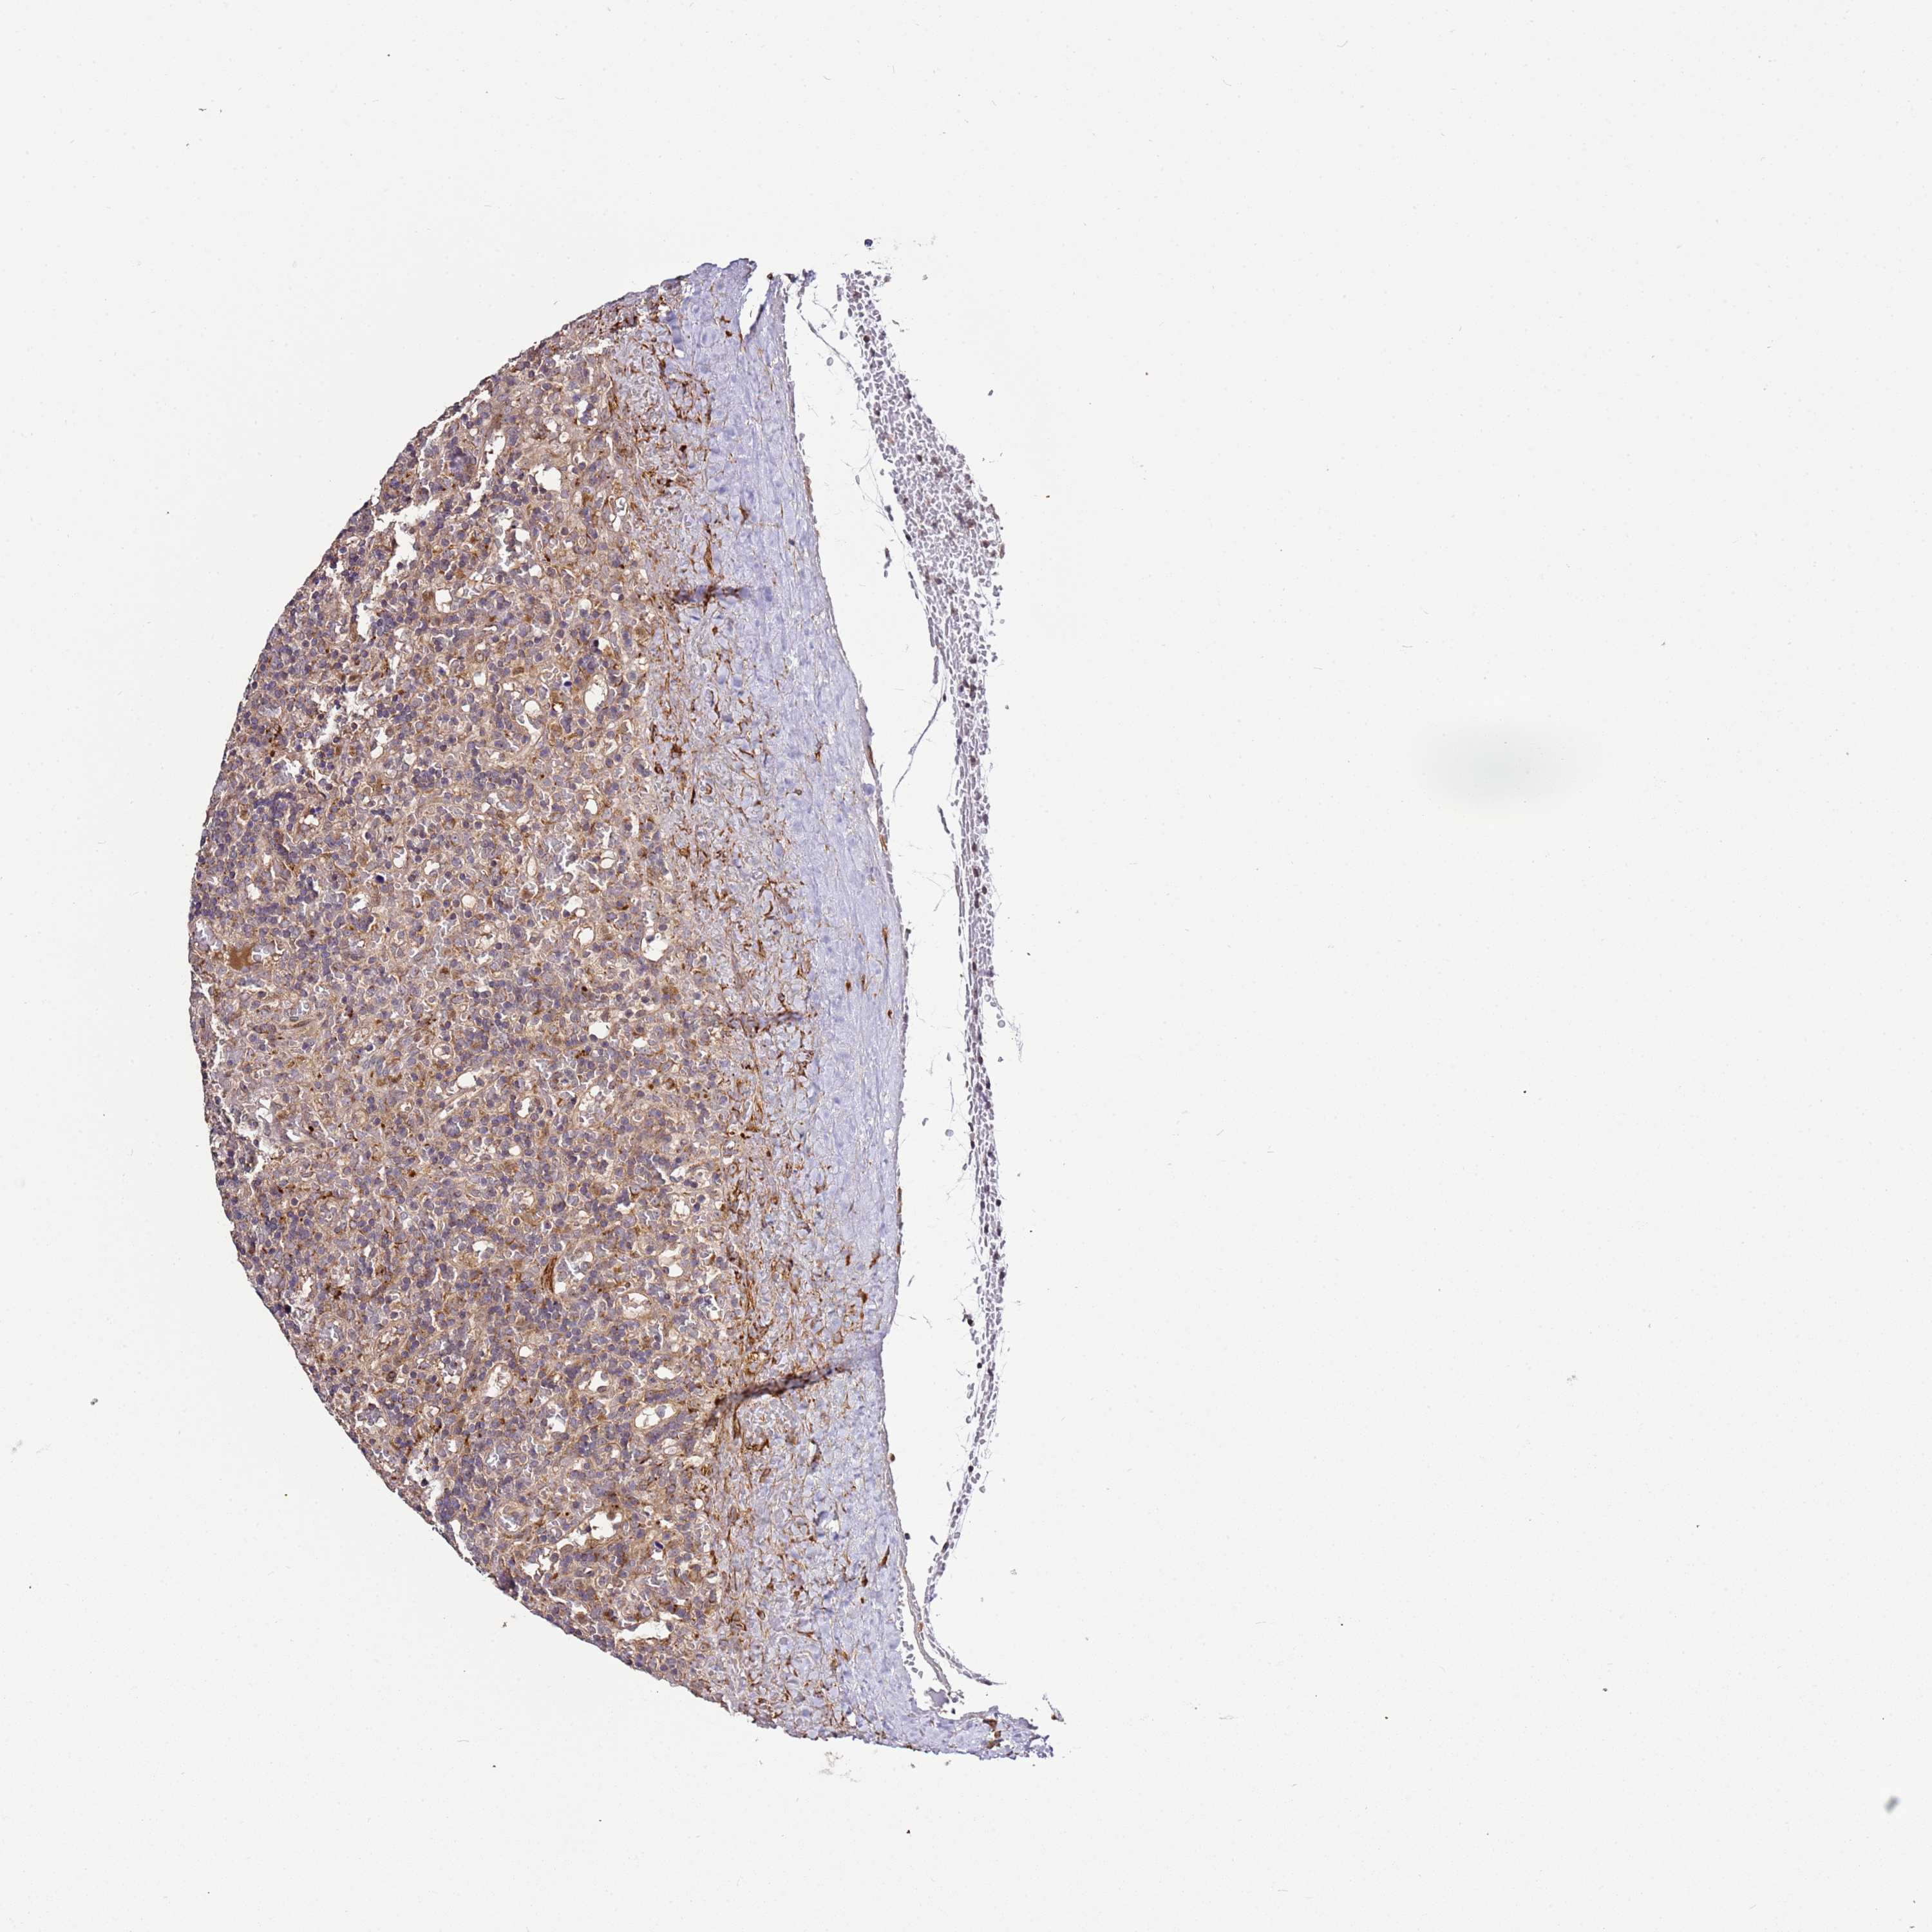

LYMPHOMA - Protein expressioni

A mouse-over function shows sample information and annotation data. Click on an image to view it in a full screen mode. Samples can be filtered based on level of antibody staining by selecting one or several of the following categories: high, medium, low and not detected. The assay and annotation is described here.

Each image is clickable and will lead to virtual microscopy that enables deeper exploration of all samples and also displays staining intensity scores, fraction scores and subcellular localization as well as patient and tissue information for each sample.

Antibody HPA047497

Staining

High

Medium

Low

Not detected

Intensity

Strong

Moderate

Weak

Negative

Quantity

>75%

75%-25%

<25%

None

Location

Nuclear

Cytoplasmic/membranous

Cytoplasmic/membranous,nuclear

Hodgkin's disease, NOS

Malignant lymphoma, non-Hodgkin's type, High grade

Malignant lymphoma, non-Hodgkin's type, Low grade